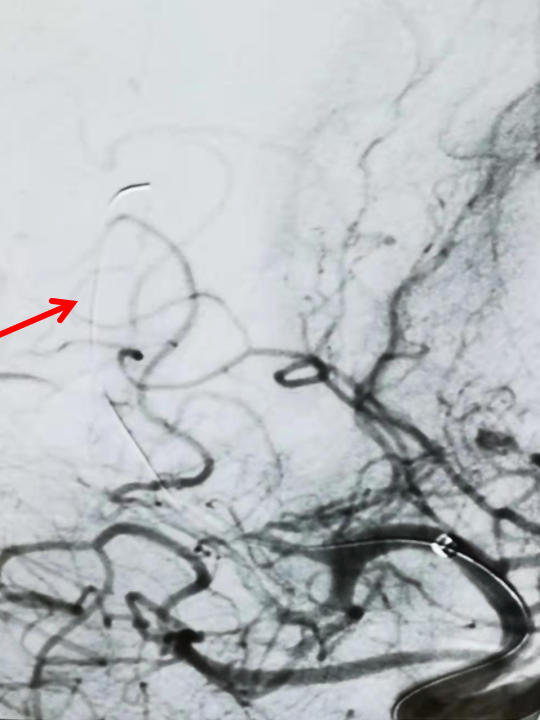

通过微导管给予路径图,而后将微导丝置于闭塞血管远端后撤出微导管(图箭头示)。